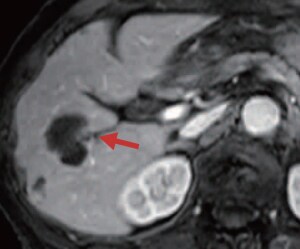

CT and EOB-MRI findings

The cancer was unifocal, but, because the patient was elderly, cTACE was performed, using a suspension of 6 mL of lipiodol, 30 mg of epirubicin, and 6 mg of mitomycin C, and GS. Simple CT (e) after 1 week showed high-concentration lipiodol accumulation in the tumor, but the therapeutic safety margin in the dorsal region was insufficient (red arrow). The dynamic CT arterial-dominant phase (f) after 4 months suggested recurrence on the dorsal side of the tumor (yellow arrow), so EOB-MRI was performed. Artifacts were generated in the arterial-dominant phase, making evaluation difficult, but in the portal-dominant phase (g) and hepatobiliary phase (h) distinct recurrence was found (blue arrow), so cTACE was performed, using a suspension of 3 mL of lipiodol, 20 mg of epirubicin, and 4 mg of mitomycin C, and GS.